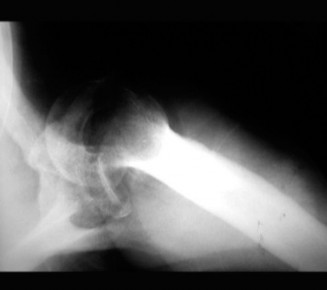

CASE 11 A 33-year-old male presents to the ED after a fall during a soccer game. He reports significant right shoulder pain and limited ROM. An x-ray taken in the ED is shown below (Fig. 2–29).

Figure 2–29

The correct answer is (A). The ED image shown in Figure 2–29 includes only an AP view of the right shoulder. In the setting of an acute injury and pain, technicians may be hesitant to obtain additional views. A single view, however, is insufficient to diagnose either a fracture, as orthogonal views are required, or a shoulder dislocation which is best seen on an axillary view (see Fig. 2–30). Answers B and C are inappropriate as a diagnosis has not been established yet and a dislocation or fracture must be conclusively ruled out. Answers D and E may be options that are exercised in the clinic but do not represent the next step in the management of this patient.

--- _Figure 2–30_A: Axillary view. B: Axillary view with annotations. Traumatic anterior instability is a common shoulder problem with an estimated incidence of 1.7%. This term encompasses both frank dislocations that require a manual reduction as well as incomplete subluxations that spontaneously reduce. It is particularly common in the young and athletic population, and it is significantly more common than other forms of instability including posterior or multidirectional instability. Understanding the natural history of anterior instability is important, as it serves as a guide to treatment. Young patients have a very high risk of recurrence; patients <20 years old have a 90% recurrence risk, between 20 and 40 years old have a 60% recurrence risk, and >40 years old have a 10% risk. Recurrent events are a predictor for arthritis and necessitate aggressive treatment, particularly in the young patient.